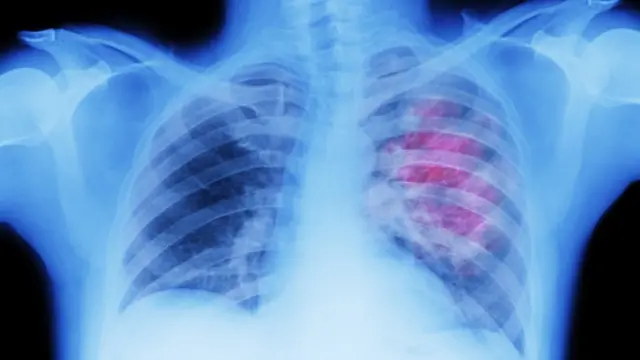

Los investigadores habían notado un vínculo entre una mejor supervivencia frente al cáncer de pulmón y una parte del sistema inmunológico, llamadas células B, que se agrupan alrededor de los tumores.

Las células B son la parte de nuestro cuerpo que fabrica anticuerpos y son más conocidas por su papel en la lucha contra las infecciones, como la covid.

Qué estaban haciendo exactamente en el cáncer de pulmón era un misterio, pero una serie de intrincados experimentos con muestras de pacientes y pruebas con animales demostraron que todavía estaban intentando combatir virus.